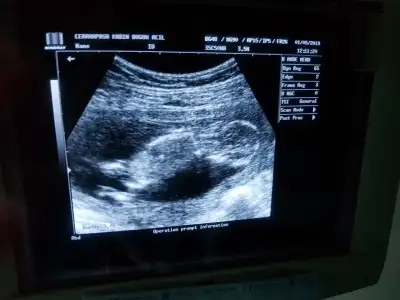

Kontrolden çıktık sata gore 12+4 ultrasona gore geriden gelen bebişim bugun 13+2 cikti :) boyu 6.5 cm olmuş ense ve burun kemiğine iyi dedi kac diye sorunca 1den kucuk merak etme sorun yok dedi doktorumkan verdim 1 hafta sonra çıkacakmış sonuç doktorum cinsiyetle ilgili de kıza benziyor ama kesin değil dedi ve ben basından beri kiz hissediyorum:) en son gittiğimde mercimek tanesi kadardı ama bugun gercekten bir bebek gordum zıplayan kayan ellerini oynatan, Rabbimin gerçekten bir mucizesi Allahım hepimize boyle guzel haberler almayi nasip etsin inşallah tekrar :)Eki Görüntüle 2264270 Eki Görüntüle 2264272 Eki Görüntüle 2264270 Eki Görüntüle 2264272